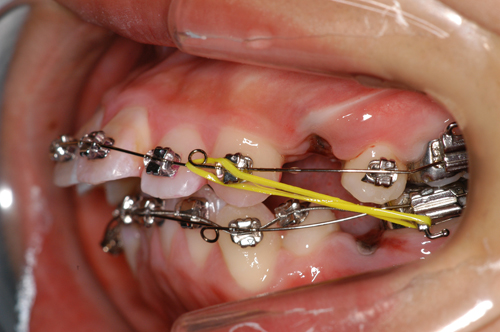

歯を抜いた場合(プロフィールの改善が困難な時)空隙の閉鎖を行います。 |

全ての歯における理想的な歯軸傾斜の達成。

(トルクとアップライトの仕上げ) |